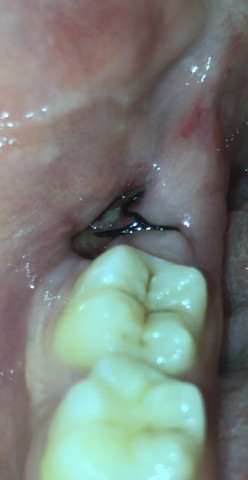

Zahn Gezogen Ist Die Wunde Entzundet Gesundheit Zahnarzt Entzundung